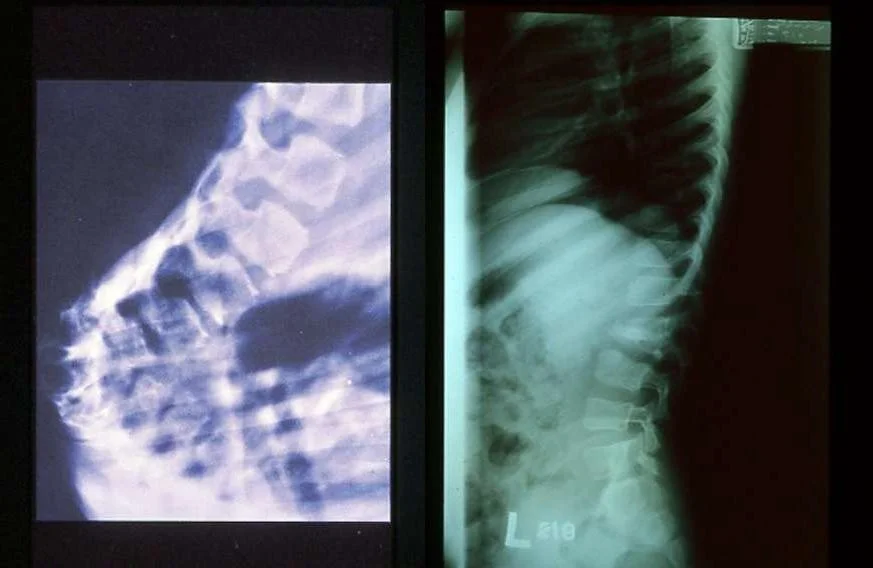

Radiology in Spinal TB (Pott’s Disease)

Spinal T.B (Pott’s Disease):

Secondary to hematogenous spread

Affect two or more adjacent vertebrae

Skip levels

Primarily does not affect the disc but eventually the disc is affected

Affects most commonly the anterior part of the vertebral endplates

Causing erosion and destruction and finally anterior wedging of the vertebrae

Infection spreads to adjacent level under the longitudinal ligaments and hematologically

The disc herniates into the weakened and destructed body and narrowing of the disc height follows

Eventually a kyphotic deformity occurs

Para vertebral abscess is common and may be distant as well

- Cervical > retropharyngeal abscess

- Lumbar > psoas abscess

Compression of the spinal cord is more likely to occur at the thoracic level

Neurological deficits occur due to the compression secondary to the deformity or compression from the abscess

Paraplegia may occur

Computerized Tomography:

- Further delineate bony destruction and sequestrum Magnetic Resonance Imaging with Contrast:

- Soft tissue mass, abscess

- Nerve root, cord status

- Distant abscess

- Non-enhanced cold abscess with enhanced peripheral ring